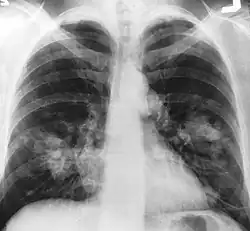

Le cancer du poumon peut être vu sur les radiographies thoraciques et le scanner. Le diagnostic est confirmé par une biopsie. Ceci se fait généralement par bronchoscopie, ou par biopsie guidée par scanner. Le traitement et le pronostic dépendent du type histologique du cancer, de son stade (degré de dissémination), et de l'état général de santé du patient.

La radiographie thoracique est la première mesure à prendre si un patient se plaint de symptômes pouvant suggérer un cancer du poumon. Ceci peut révéler une masse évidente, un élargissement du médiastin (qui suggère une extension aux ganglions lymphatiques qui s'y trouvent), une atélectasie (affaissement), une inflammation (pneumonie) ou un épanchement pleural. En l'absence de signes radiographiques, mais si les soupçons sont élevés (par exemple, un gros fumeur avec hémoptysie), une bronchoscopie ou un scanner peuvent donner l'information nécessaire. La bronchoscopie ou la biopsie guidée par scanner sont souvent utilisées pour identifier le type de tumeur[3].

Le diagnostic différentiel pour les patients qui présentent des anomalies de la radiographie thoracique consiste à distinguer le cancer du poumon des maladies non malignes. Ces dernières peuvent être des infections, telles que la tuberculose ou la pneumonie, ou des inflammations comme la sarcoïdose. Ces maladies peuvent donner lieu à des lymphadénopathies du médiastin, ou à des nodules du poumon, qui peuvent imiter des cancers du poumon[4]. Le cancer du poumon peut par contre être une trouvaille incidentelle : un nodule pulmonaire solitaire (lésion en « pièce de monnaie ») vu sur une radiographie du thorax ou un scanner pris pour une tout autre raison.